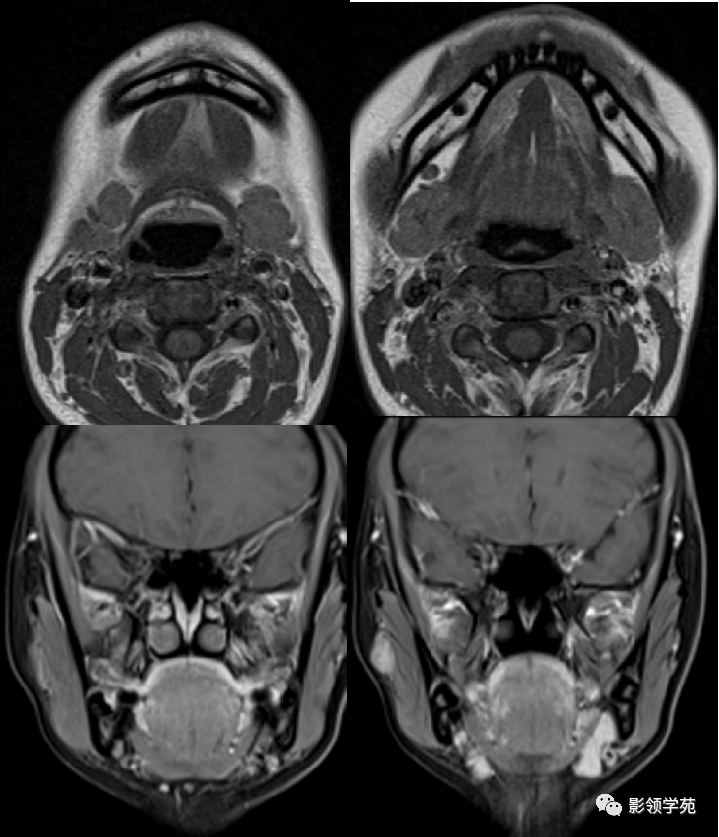

舌、口底影像解剖及常见疾病影像诊断